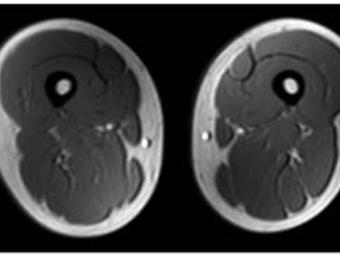

Fatty Liver Disease despite a Normal Weight